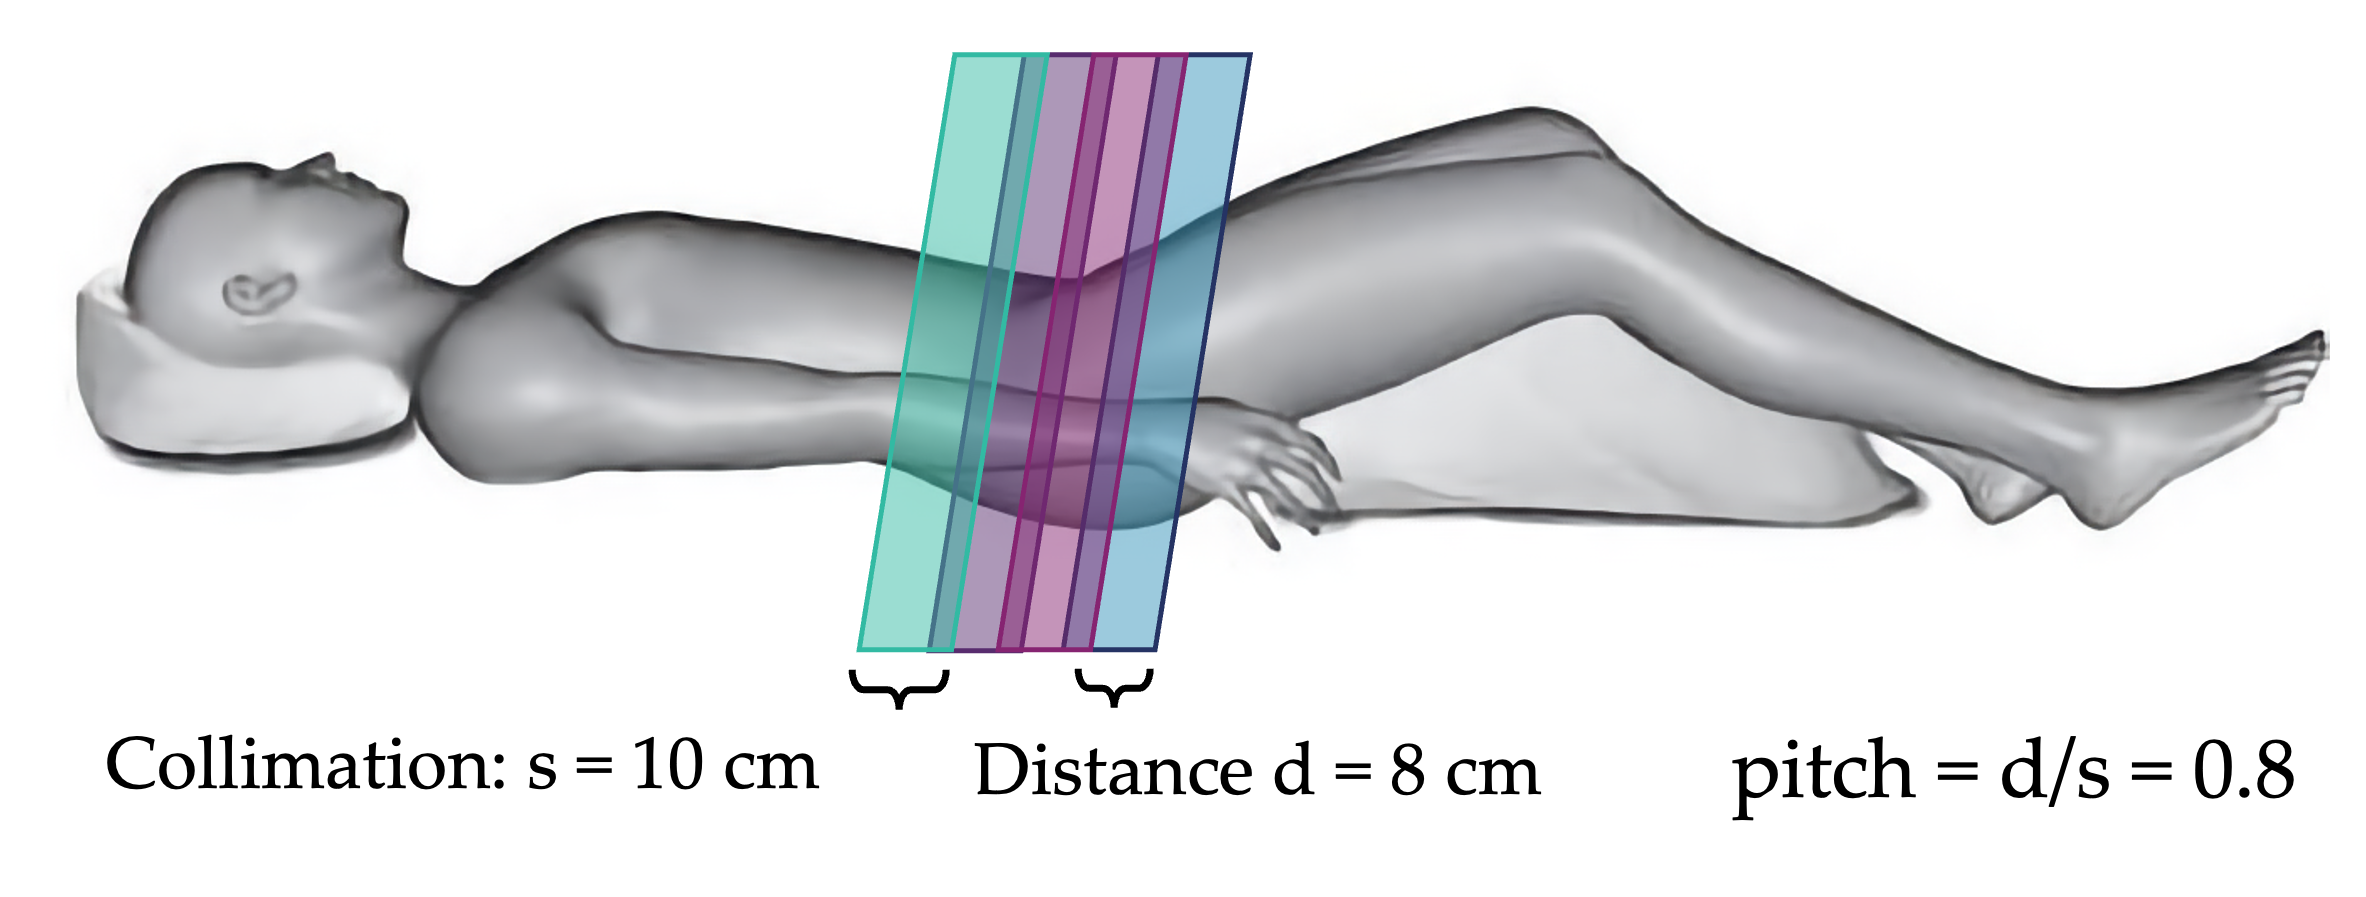

Helical/Spiral

More commonly, modern CT scanners use a helical motion to acquire images. In this setup, the bed moves continuously while the tube-detector system rotate. This process results in faster imaging and greater dose control. The helical pitch determines the effective slice thickness and dose. Pitch is the distance the bed moves during one beam rotation, divided by the beam collimation. For overlapping motion, pitch is less than 1. Contiguous motion has pitch equal one, and extended motion has pitch greater than 1. The dose is roughly proportional to 1/pitch, such that higher pitches result in lower dose (less overlap). The final image slices are still axial and are reconstructed by averaging CT projections taken 180 degrees apart.

Question: if collimation is 10 cm and bed moves 20 cm per rotation, what is the pitch?

pitch = bed motion / collimation = 20 cm / 10 cm = 2 (extended)